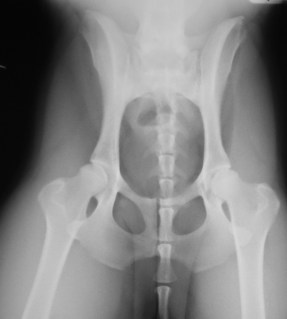

Για την αποκατάσταση της σπονδυλικής στήλης επιλέχθηκε η μέθοδος της τροποποιημένης τμηματικής νωτιαίας σταθεροποίησης. Σύμφωνα με αυτή τη μέθοδο, μετά την ανάταξη του εξαρθρήματος, ήλοι κεκαμμένοι σε ορθή γωνία τοποθετήθηκαν εκατέρωθεν των ακανθωδών αποφύσεων των οσφυϊκών σπονδύλων και προσδέθηκαν σε αυτούς με σύρμα, το οποίο είχε προηγουμένως περαστεί από οπές που είχαν διανοιχτεί στις αρθρικές και στην ακανθώδη απόφυση κάθε σπονδύλου. Οι ήλοι στερεώθηκαν σε τρείς σπονδύλους κεφαλικώς του εξαρθρήματος, στο σπόνδυλο ουραίως του εξαρθρήματος και στο ιερό οστό. Το κάθετο προς τη σπονδυλική στήλη τμήμα των ήλων διήλθε από οπές, οι οποίες είχαν διανοιχθεί στις πτέρυγες των λαγονίων οστών (Εικ. 4 και 5).

Εικ. 4: Τροποποιημένη τμηματική νωτιαία σταθεροποίηση

Για τα κατάγματα των σπονδύλων δεν ελήφθη ιδιαίτερη μέριμνα. Η οσφυϊκή μοίρα της σπονδυλικής στήλης ακτινογραφήθηκε μετεγχειρητικώς ώστε να επιβεβαιωθεί η ανάταξη του εξαρθρήματος (Εικ. 6).

Εικ. 6: Μετεγχειρητική ακτινογραφία